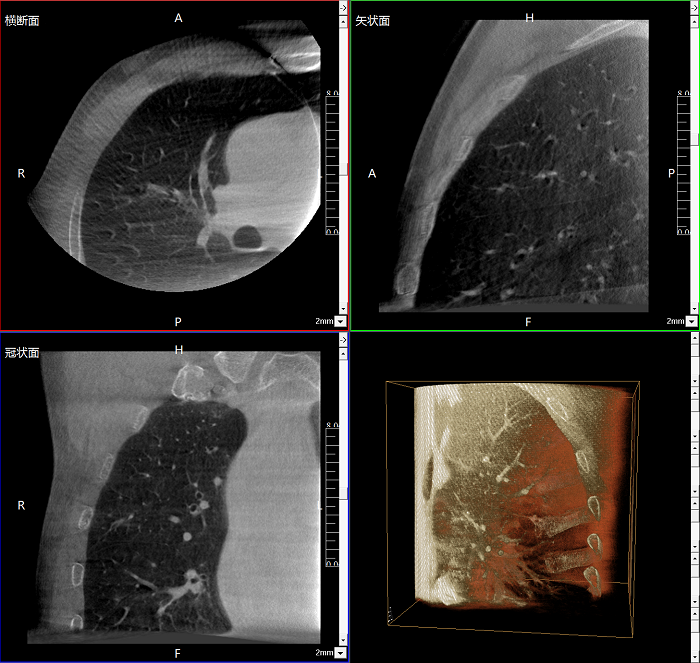

三維成像 全面觀察

任意視角、任意切面觀察

術(shù)中實(shí)時(shí)生成橫斷面、矢狀面、冠狀面及三維影像,可在任意切面、任意角度評(píng)估植入物和解剖結(jié)構(gòu)的相對(duì)位置。

術(shù)中CT檢查 減少翻修概率

通過術(shù)中三維影像的檢查,可以立即發(fā)現(xiàn)植入物的錯(cuò)位,減少不必要的第二次手術(shù),減少并發(fā)癥概率以及感染風(fēng)險(xiǎn)。